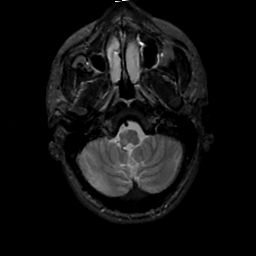

MR Study #2, February 17, 1991 -- Slice #7

[Home][Help][Clinical][Tour 1][Tour 2] Slice 7